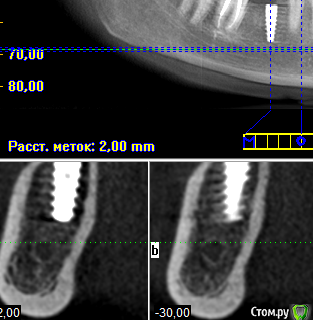

Елена83 Опубликовано 6 февраля, 2016 Автор Поделиться Опубликовано 6 февраля, 2016 вроде симпатичноне переживайте раньше времени сходите на очную консультацию к ортопедуСпасибо!Смутило еще, что с правой стороны(тот же 6 зуб) имплант стоит вполне вертикально без углов. Если можно, посмотрите еще пожалуйста его снимок, темные зоны вокруг импланта означают что он не прижился? Ссылка на комментарий

red_butler Опубликовано 6 февраля, 2016 Поделиться Опубликовано 6 февраля, 2016 Это искажения вызванные металлом. Ссылка на комментарий